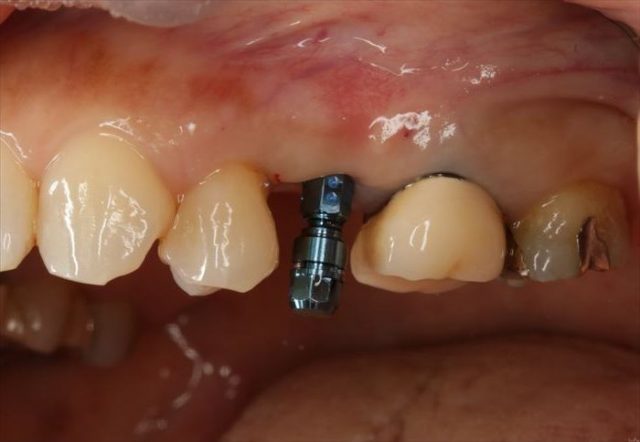

埋入を終えました。青いパーツは埋入時用のジグです。

咬合面観です。

近遠心幅が狭いのでポジションの位置決めには緊張します。

挿入ジグを外しました。